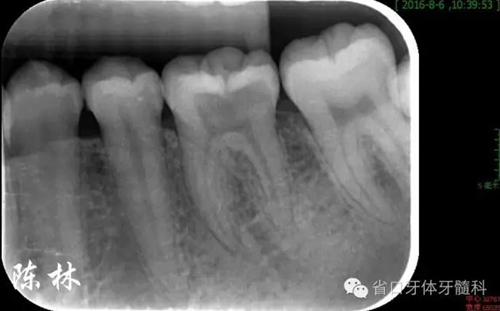

(圖1)術(shù)前口內(nèi)照:36牙合面窩溝點隙齲損(頜面基本完整,無明顯缺損)

(圖2)術(shù)前根尖片:示36齲損及髓,根周無明顯低密度影